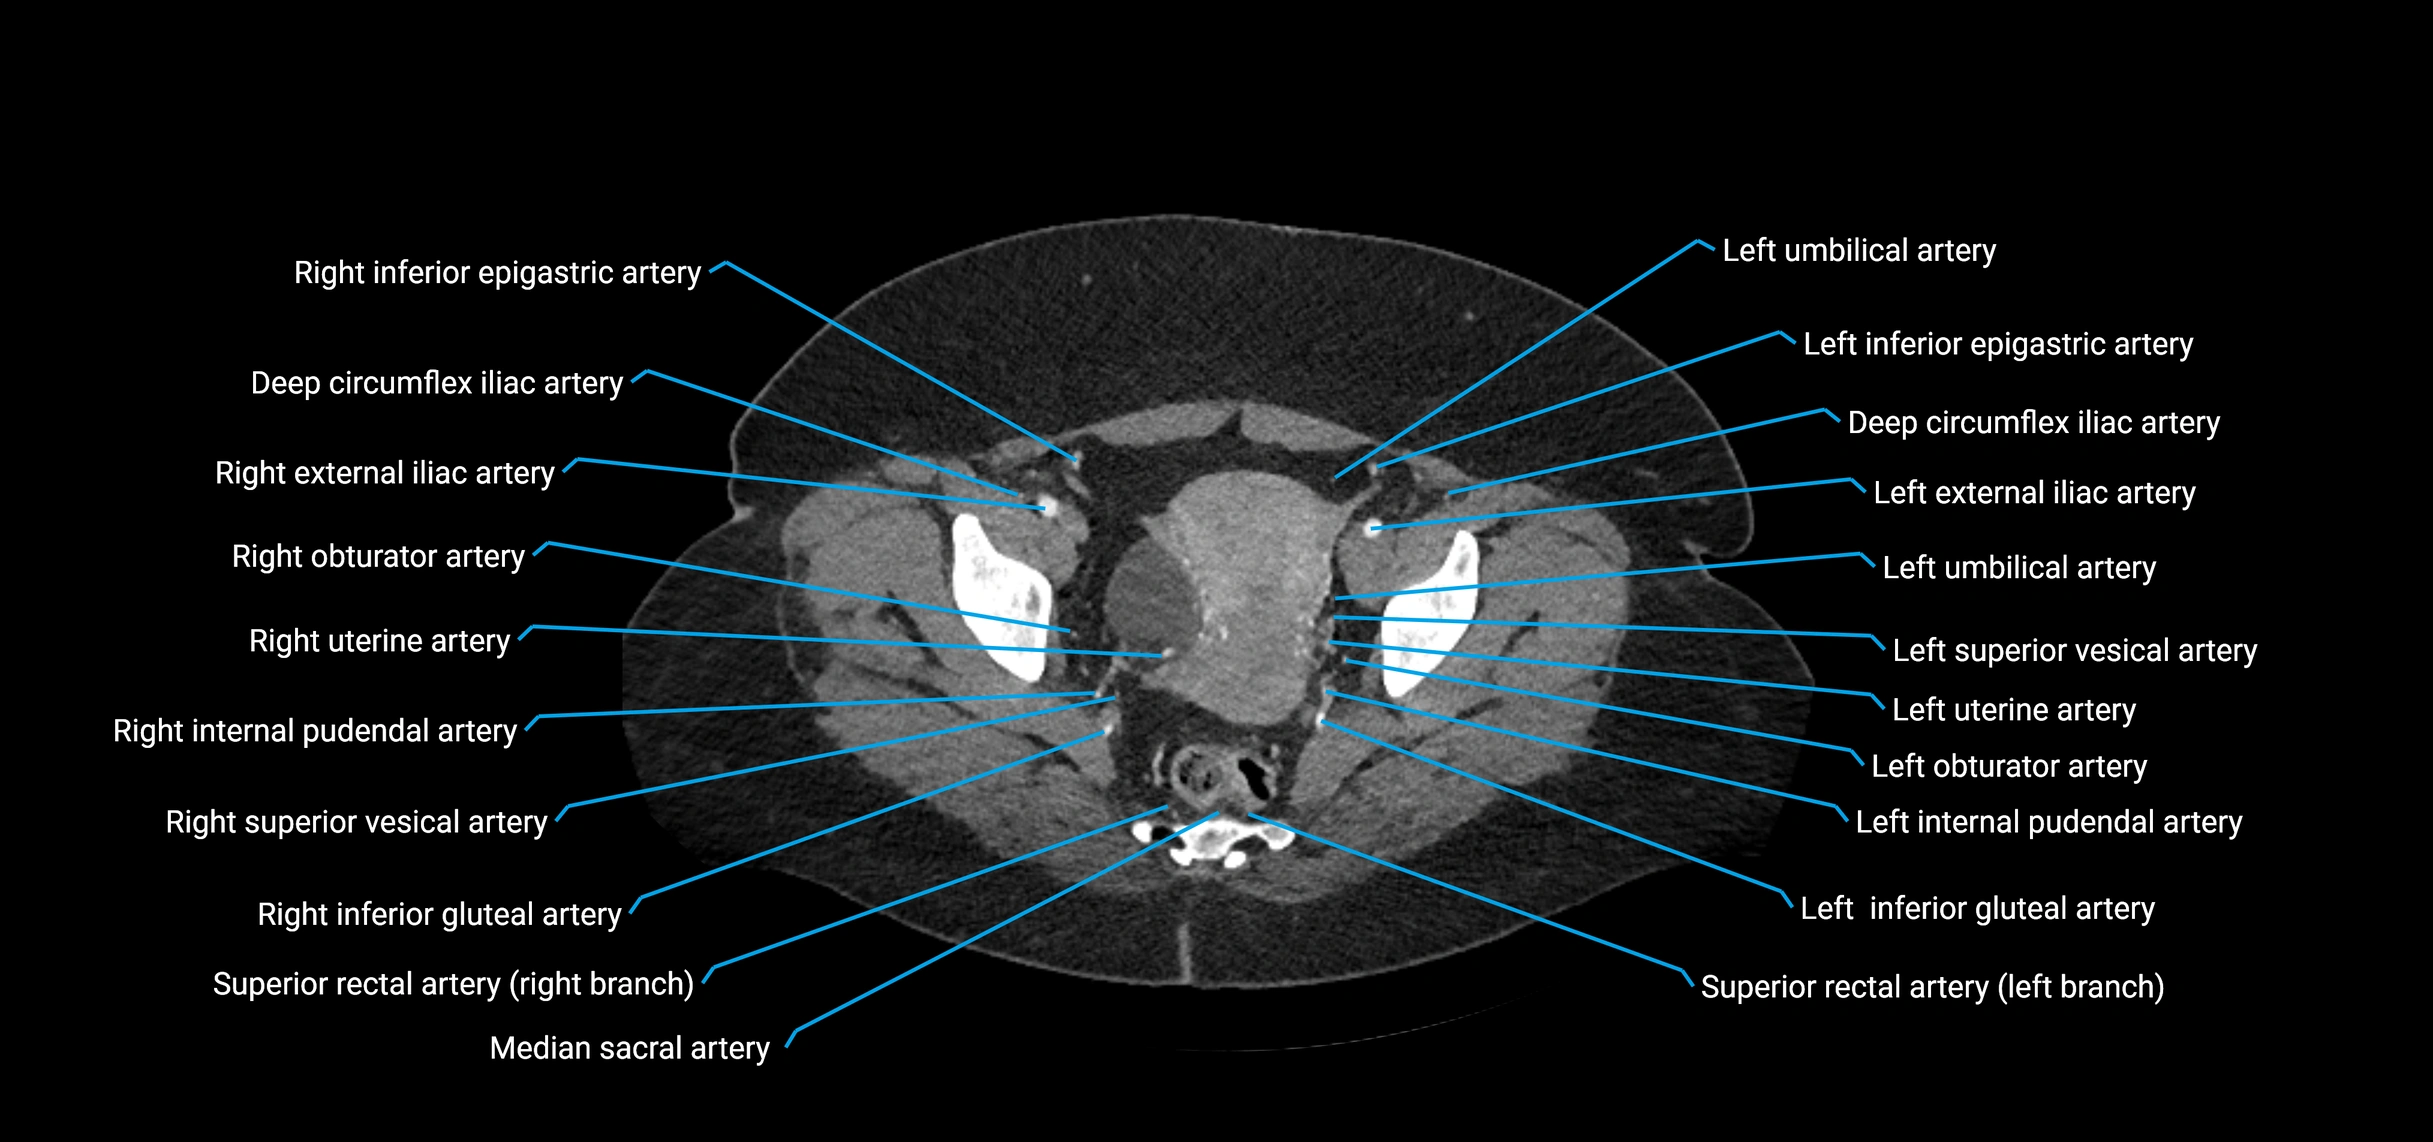

CT images

image

Contrast-enhanced CT (CTA):

• Gold standard for abdominal aortic imaging

• Provides excellent detail of lumen, wall, aneurysm, thrombus, and branch vessels

• Multiplanar and 3D reconstructions help in aneurysm measurement, stent graft planning, and dissection evaluation